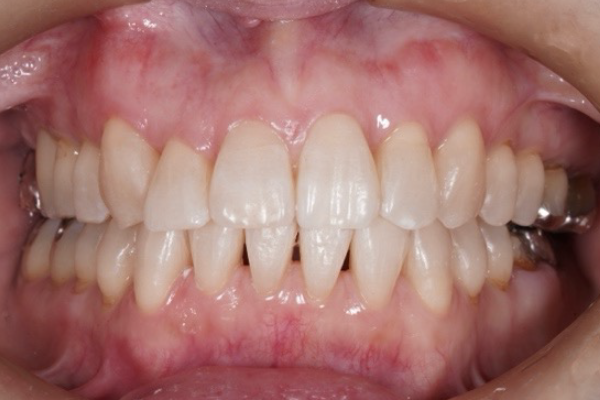

矯正治療後

Aさんは2年の治療を経て、歯並びが整いました。

笑顔が増えて、自信を持てるようになりました。

前歯で物を咬むことも出来るようになりました。もっと早くやれば良かったです!